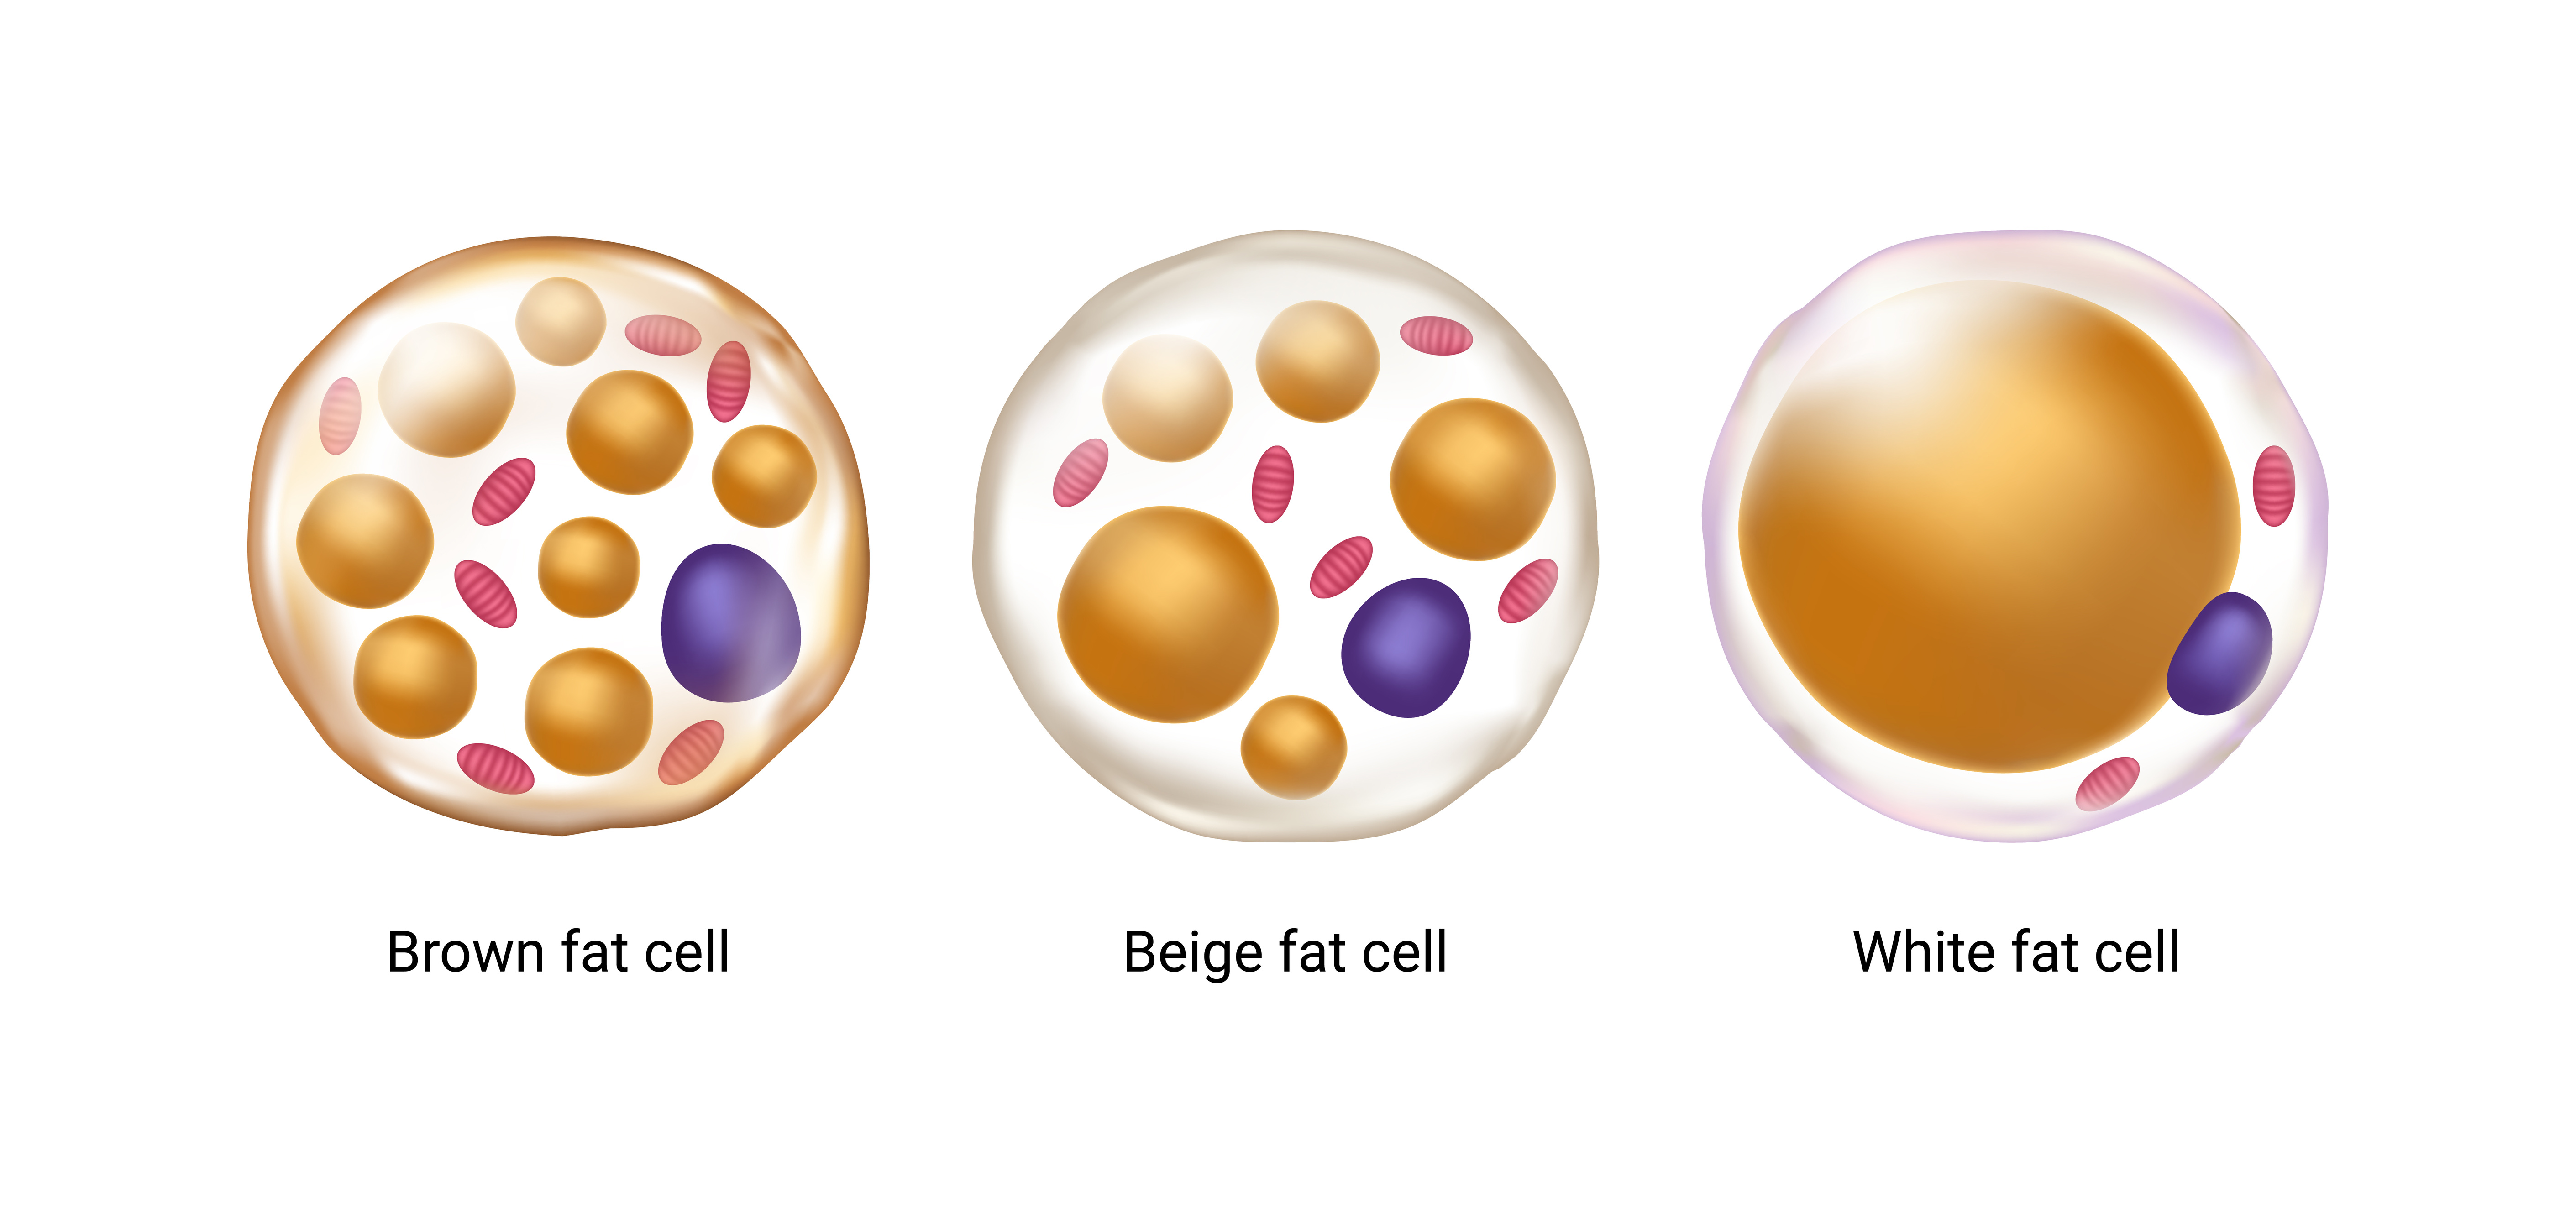

There are actually three types of body fat: white, brown, and beige. While white fat — the most common — is specialized solely for storage and hormonal function, beige and brown produce heat to keep us warm. Brown fat is stored in deposits whose locations are specified prior to birth (often around the collarbone and spine), while beige fat develops within stores of white fat. In fact, white fat cells actually convert to beige cells when environmental temperatures drop and revert back when temperatures rise.